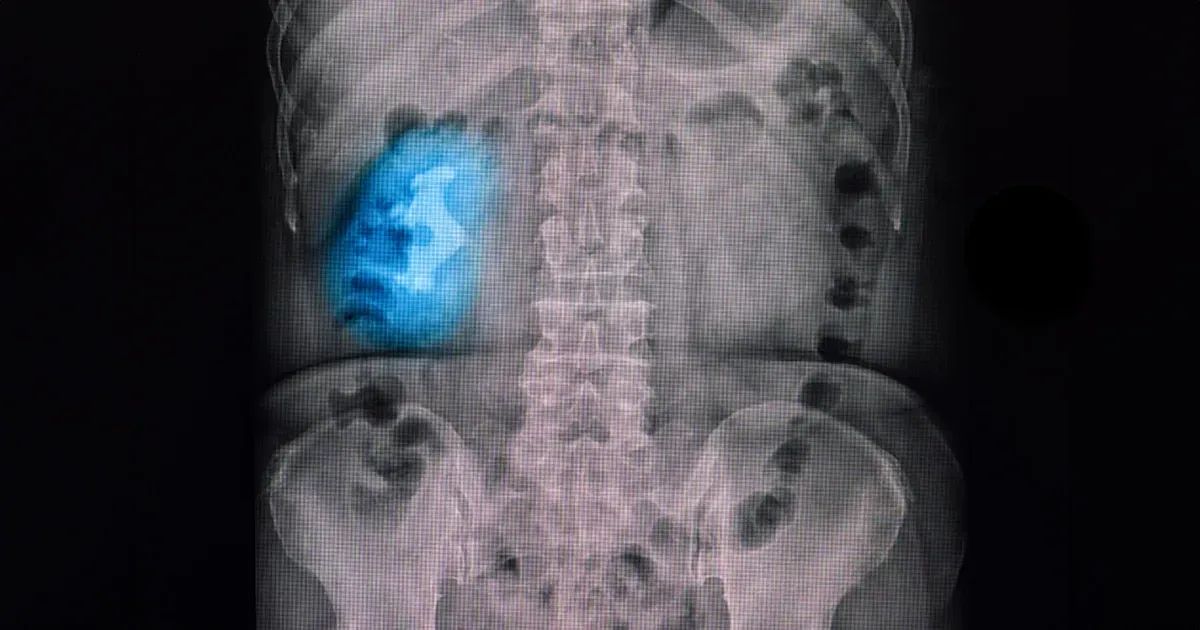

Ne esistono quattro tipi principali: ossalato di calcio, acido urico, struvite e cisteina. Tra questi, i calcoli di struvite ne assumono l'aspetto più caratteristico, formando grandi strutture ramificate note come "calcoli a corna di cervo", che riempiono gli spazi interni dei reni.

I calcoli a corna di cervo, chiamati così per la loro caratteristica forma "simile a un palco di corno", sono composti principalmente da struvite (fosfato di ammonio e magnesio). Si formano solitamente a causa di infezioni croniche del tratto urinario (UTI), in particolare dovute a batteri che producono l'enzima ureasi, come il Proteus mirabilis. Questo enzima scompone l'urea, aumentando la concentrazione di ammoniaca nelle urine, innalzandone il pH e creando un ambiente alcalino favorevole alla formazione di calcoli.

L'anatomia dei calcoli a corna di cervo complica il trattamento. Si ramificano nella pelvi renale, un'area a forma di imbuto del rene dove l'urina viene convogliata negli ureteri e trasportata nella vescica dove si conserva. Nel momento in cui le pelvi renali o gli ureteri sono bloccati, si verificherà un gonfiore dei reni. Questi calcoli possono anche ostruire i calici, dove inizia la raccolta dell'urina. Il gonfiore di queste aree, chiamato caliectasia, se non trattato può portare a insufficienza renale, pertanto è importante una diagnosi e un trattamento tempestivi.

Queste condizioni metaboliche in combinazione a cattive abitudini alimentari o disidratazione rendono ancora più probabile la formazione di calcoli. La diagnosi prevede l'esame delle urine e l'utilizzo della diagnostica per immagini per valutare sia la presenza che l'infezione dei calcoli. L'analisi delle urine verifica la presenza di batteri e livelli elevati di pH, forti indici di calcoli correlati a infezioni. L'imaging tramite raggi X, ultrasuoni o TAC rivela la forma, le dimensioni e la posizione del calcolo all'interno del rene.